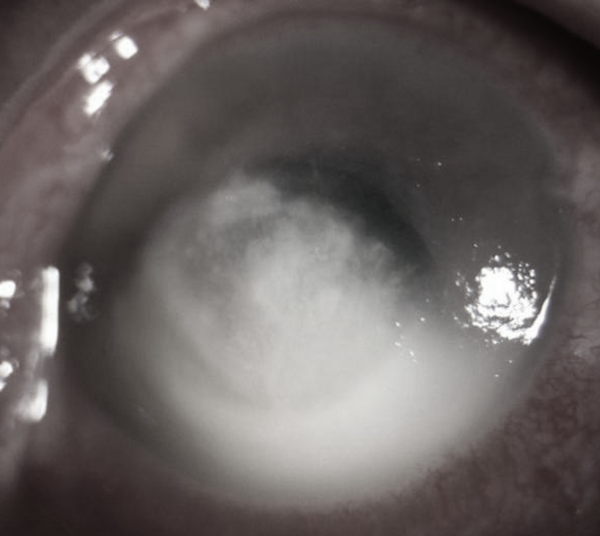

患者系49岁男性,右眼眼红、轻微眼痛、伴畏光流泪1月,加重10天,外院保守治疗效果不佳,病情加重,慕名来到我院马君择副教授门诊求诊。经过仔细询问病史以及眼科常规裂隙灯检查后,马君择副教授以“右眼真菌性角膜溃疡、右眼前房积脓”之诊断将患者收住入院。

入院时患者右眼视力仅有眼前手动,立即行角膜清创,予局部抗真菌药物点眼,辅以促进生长、散瞳、抗炎等治疗,病情一过性好转,视力恢复至眼前指数,但由于患者病程长,真菌感染已穿透角膜深入前房,遂行结膜瓣遮盖术,但因角膜溃疡炎症反应强烈,术后5天,结膜瓣完全溶解。患者眼后节未见明显异常,行角膜移植术可清除感染灶,恢复部分视力,与患者充分沟通后,患者同意行角膜移植术。随后马君择副教授团队经术前周密计划,术中与手术室密切配合,为患者顺利施行了角膜移植术。术后继续抗真菌、抗排斥反应、促进角膜生长治疗,病情好转,顺利出院。出院时患者裸眼视力0.06,2周后复查,恢复良好,裸眼视力0.1,患者十分满意。